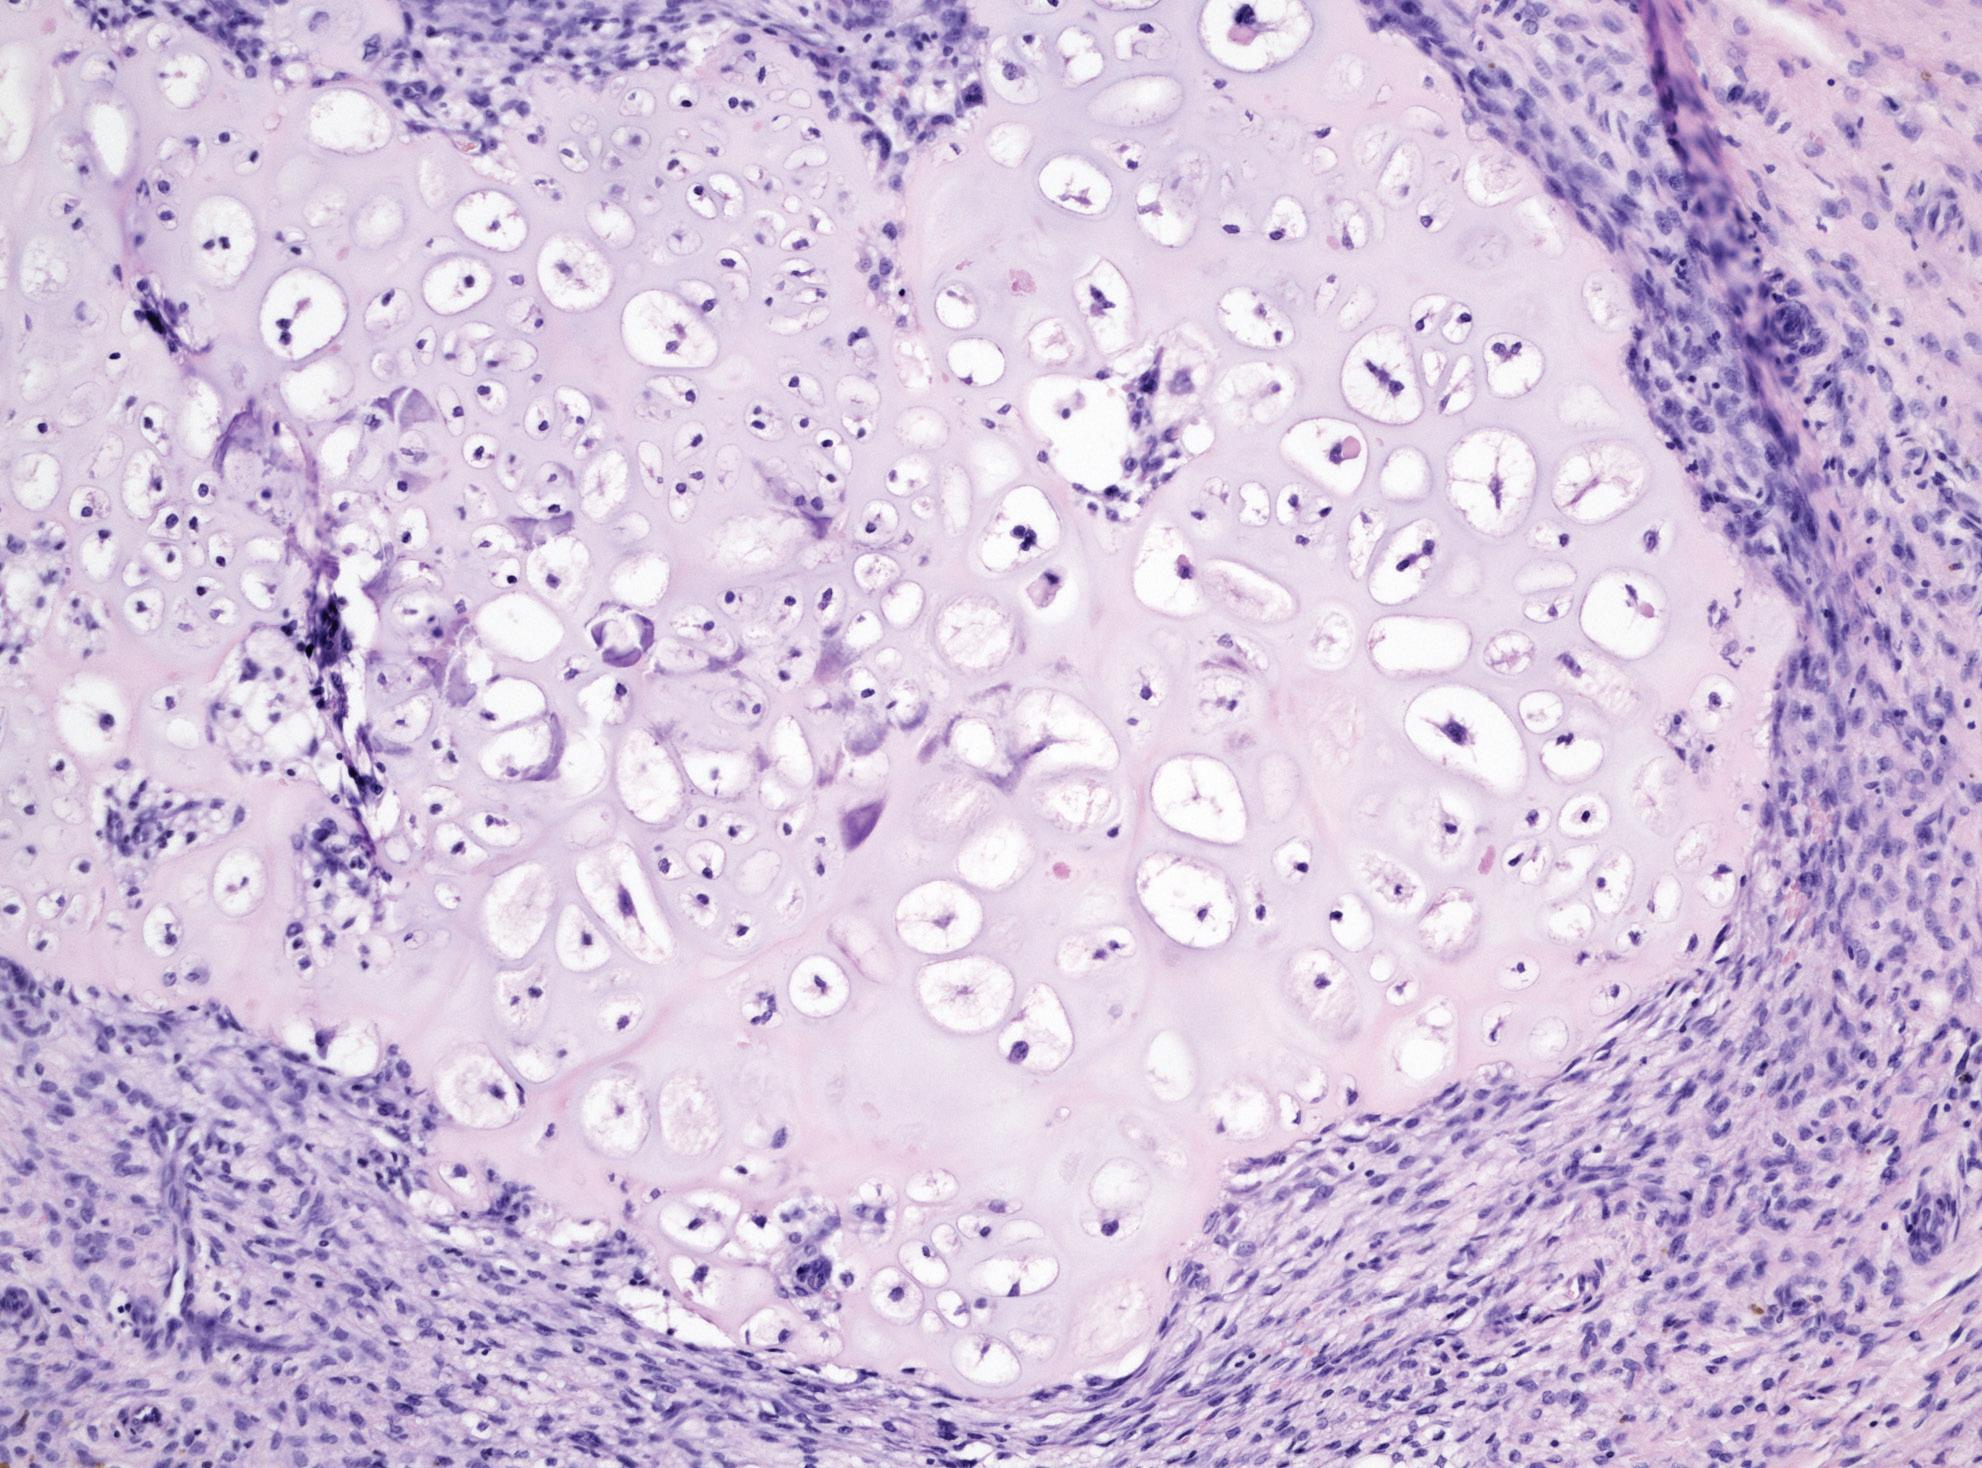

Moč pro cytologické vyšetření byla ihned po odběru fixována 1% roztokem merth io látu sodného (koncentrace cca 1 ml merthiolátu sodného na 100 ml moči). Vzorky byly po co nejkratší dobu skladovány v chladu (v lednici, do 4 °C) a urychleně transportovány na oddělení patologie. Zde byl materiál zpracován metodou cytocentrifugace, zhotoveny byly celkem čtyři cytologické preparáty, které byly barveny metodou dle Papanicolaoua. Všechny cytologické preparáty byly hodnoceny specializovaným uropatologem (KP) a klasifikovány pomocí Pařížské klasifikace pro reportování močových cytologií (tab.  1). Pro účely této studie byly za „pozitivní“ považovány močové cytologie hodnocené v rámci kategorií atypické uroteliální buňky (AUC – atypical urothelial cells), suspektní pro high-grade UC (SHGUC) a high-grade UC (HGUC). U pacientů, u nichž byla v jednom časovém období provedena více než jedna močová cytologie, byl do studie použit vždy „nejhorší“ výsledek (tj. pro statistické hodnocení byly upřednostněny výsledky z kategorie AUC, SHGUC, HGUC).

Materiál pro histologické vyšetření byl zpracován dle klasického schématu, fixován ve 4% roztoku formaldehydu

a zalitý parafínem. Z parafínových bločků byly na mikrotomu krájeny řezy tloušťky 1–2 µm a tyto obarveny v hematoxylinu a  eozinu. Histologická klasifikace bioptického materiálu byla provedena v souladu se Světovou zdravotnickou organizací (WHO – World Health Organisation) 2016/2022 a současně i s WHO 1973 dle doporučení EAU.